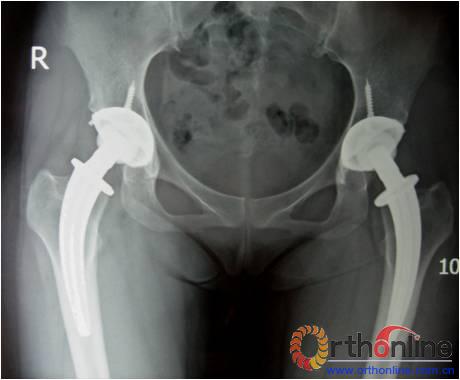

图1

图2

图3

图4

图5

图6

图为:方某,女,21岁,双侧激素性股骨头坏死,ARCO III-C期,C.F.P. 股骨假体THA前后双髋X线摄片。

图1、图2:术前;图3:术后;图4:术后3个月;图5:术后6个月;图6:术后1.2年